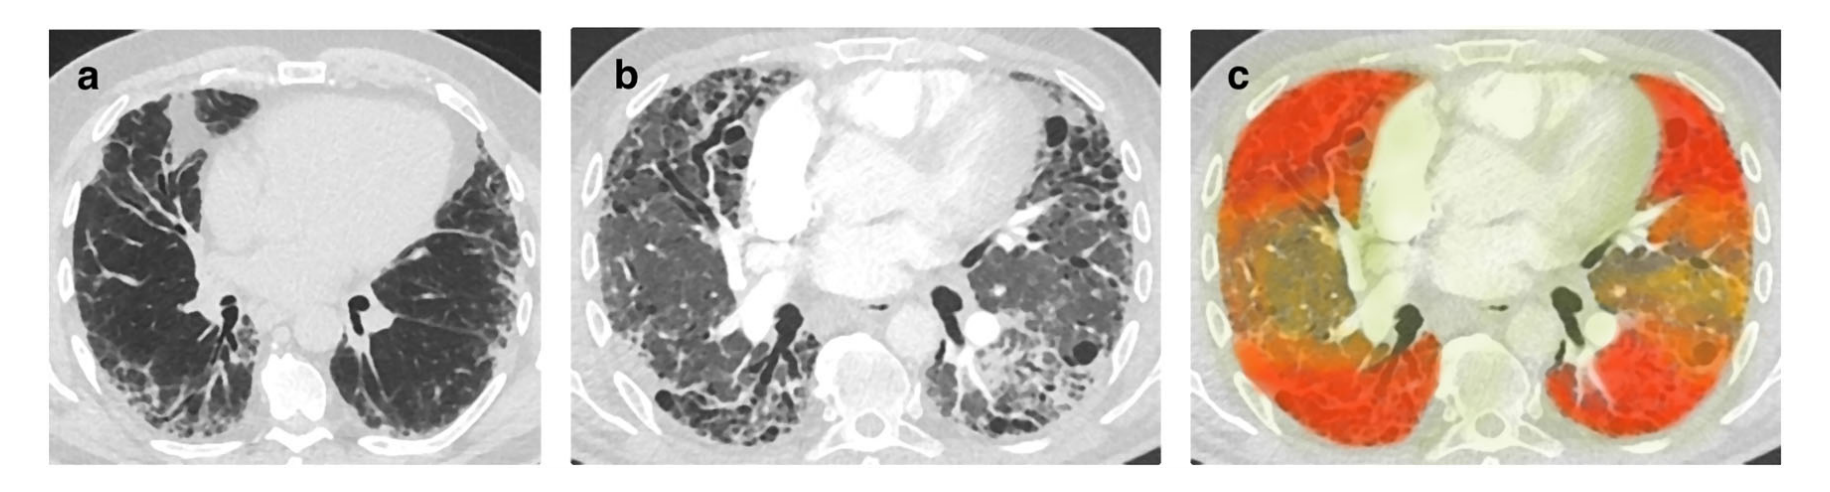

Fig. 1 展示了一种称为“增量显著性图”(delta saliency map)的新方法,它用于改善对纵向医学成像数据的解释。

在这个例子中,考虑的是间质性肺纤维化的病例:

- 图片 (a) 是在大约两年前拍摄的。

- 图片 (b) 是在两年后拍摄的,期间病情有显著进展。

- 图片 © 是增量显著性图,它通过黄色、橙色和红色的叠加颜色来展示病情的进展。

增量显著性图的特点是:

- 它能够反映出疾病在时间上的发展变化。

- 它使用颜色的深浅来表示不同区域对AI分类结果的贡献度。在这个例子中,受影响较重的肺的前部和背部区域以及胸膜下区域,预计对分类结果的贡献最大,因此这些区域用颜色的不透明度最高。

- 相比之下,肺外区域对分类结果的贡献较小,因此在图中的叠加颜色较轻。

这种图的目的是提供一个直观的方式来展示和理解AI模型是如何根据随时间变化的医学影像数据来做出预测的,从而增强了模型的可解释性。